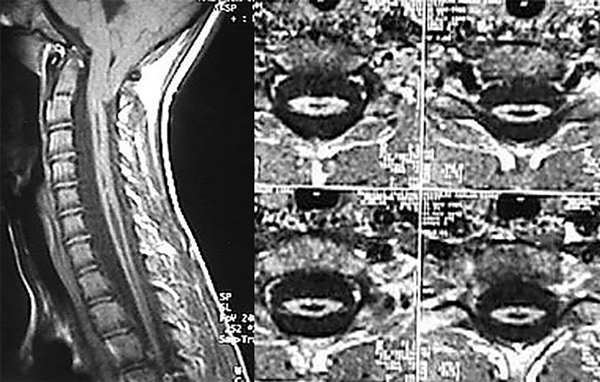

A la edad de 10 años y 6 meses, el niño presentó hiperestesia cutánea abdominal izquierda e hipotrofia de cintura escapular, asociados a signo de Babinsky bilateral. Se recomendó realizar cirugía de la malformación de Chiari, pero la familia rechazó dicha propuesta de tratamiento. Un año después, sorpresivamente, el control con RM mostró una marcada reducción del tamaño y diámetro de la siringomielia cervicotorácica, cuyo aspecto era fusiforme (Figura 2).

Figura 2. Cortes sagital y axiales de RM en los que se evidencia el colapso de la cavidad.